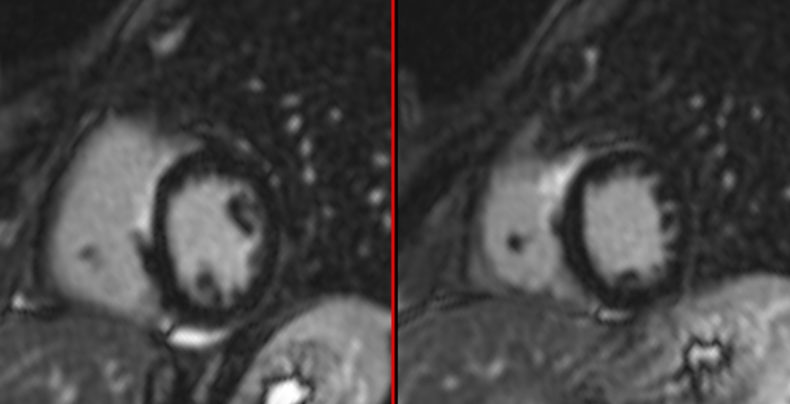

Cardiac Sarcoid